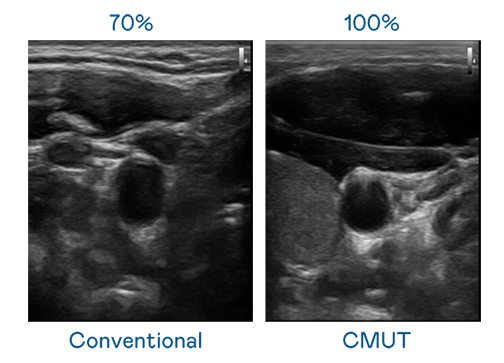

CMUT 技术是一种用电容式微机电元件来产生超音波讯号的技术。与传统 PZT 压电式技术相比,CMUT 频宽增加 30%,更宽频的超音波讯号让影像解析度大幅提升,是实现高影像品质医疗超音波扫描、促进精准医疗发展的关键技术。

大频宽带来超清晰影像

超音波影像的解析度高低,首先取决于探头能发出的讯号频宽。51爆料吃瓜黑料 CMUT 可提供高清晰的超音波讯号,提供高频宽、高灵敏度、影像纹理细节更高的超音波影像,协助医护人员缩短影像判读时间及利用精准的医疗影像进行诊断。